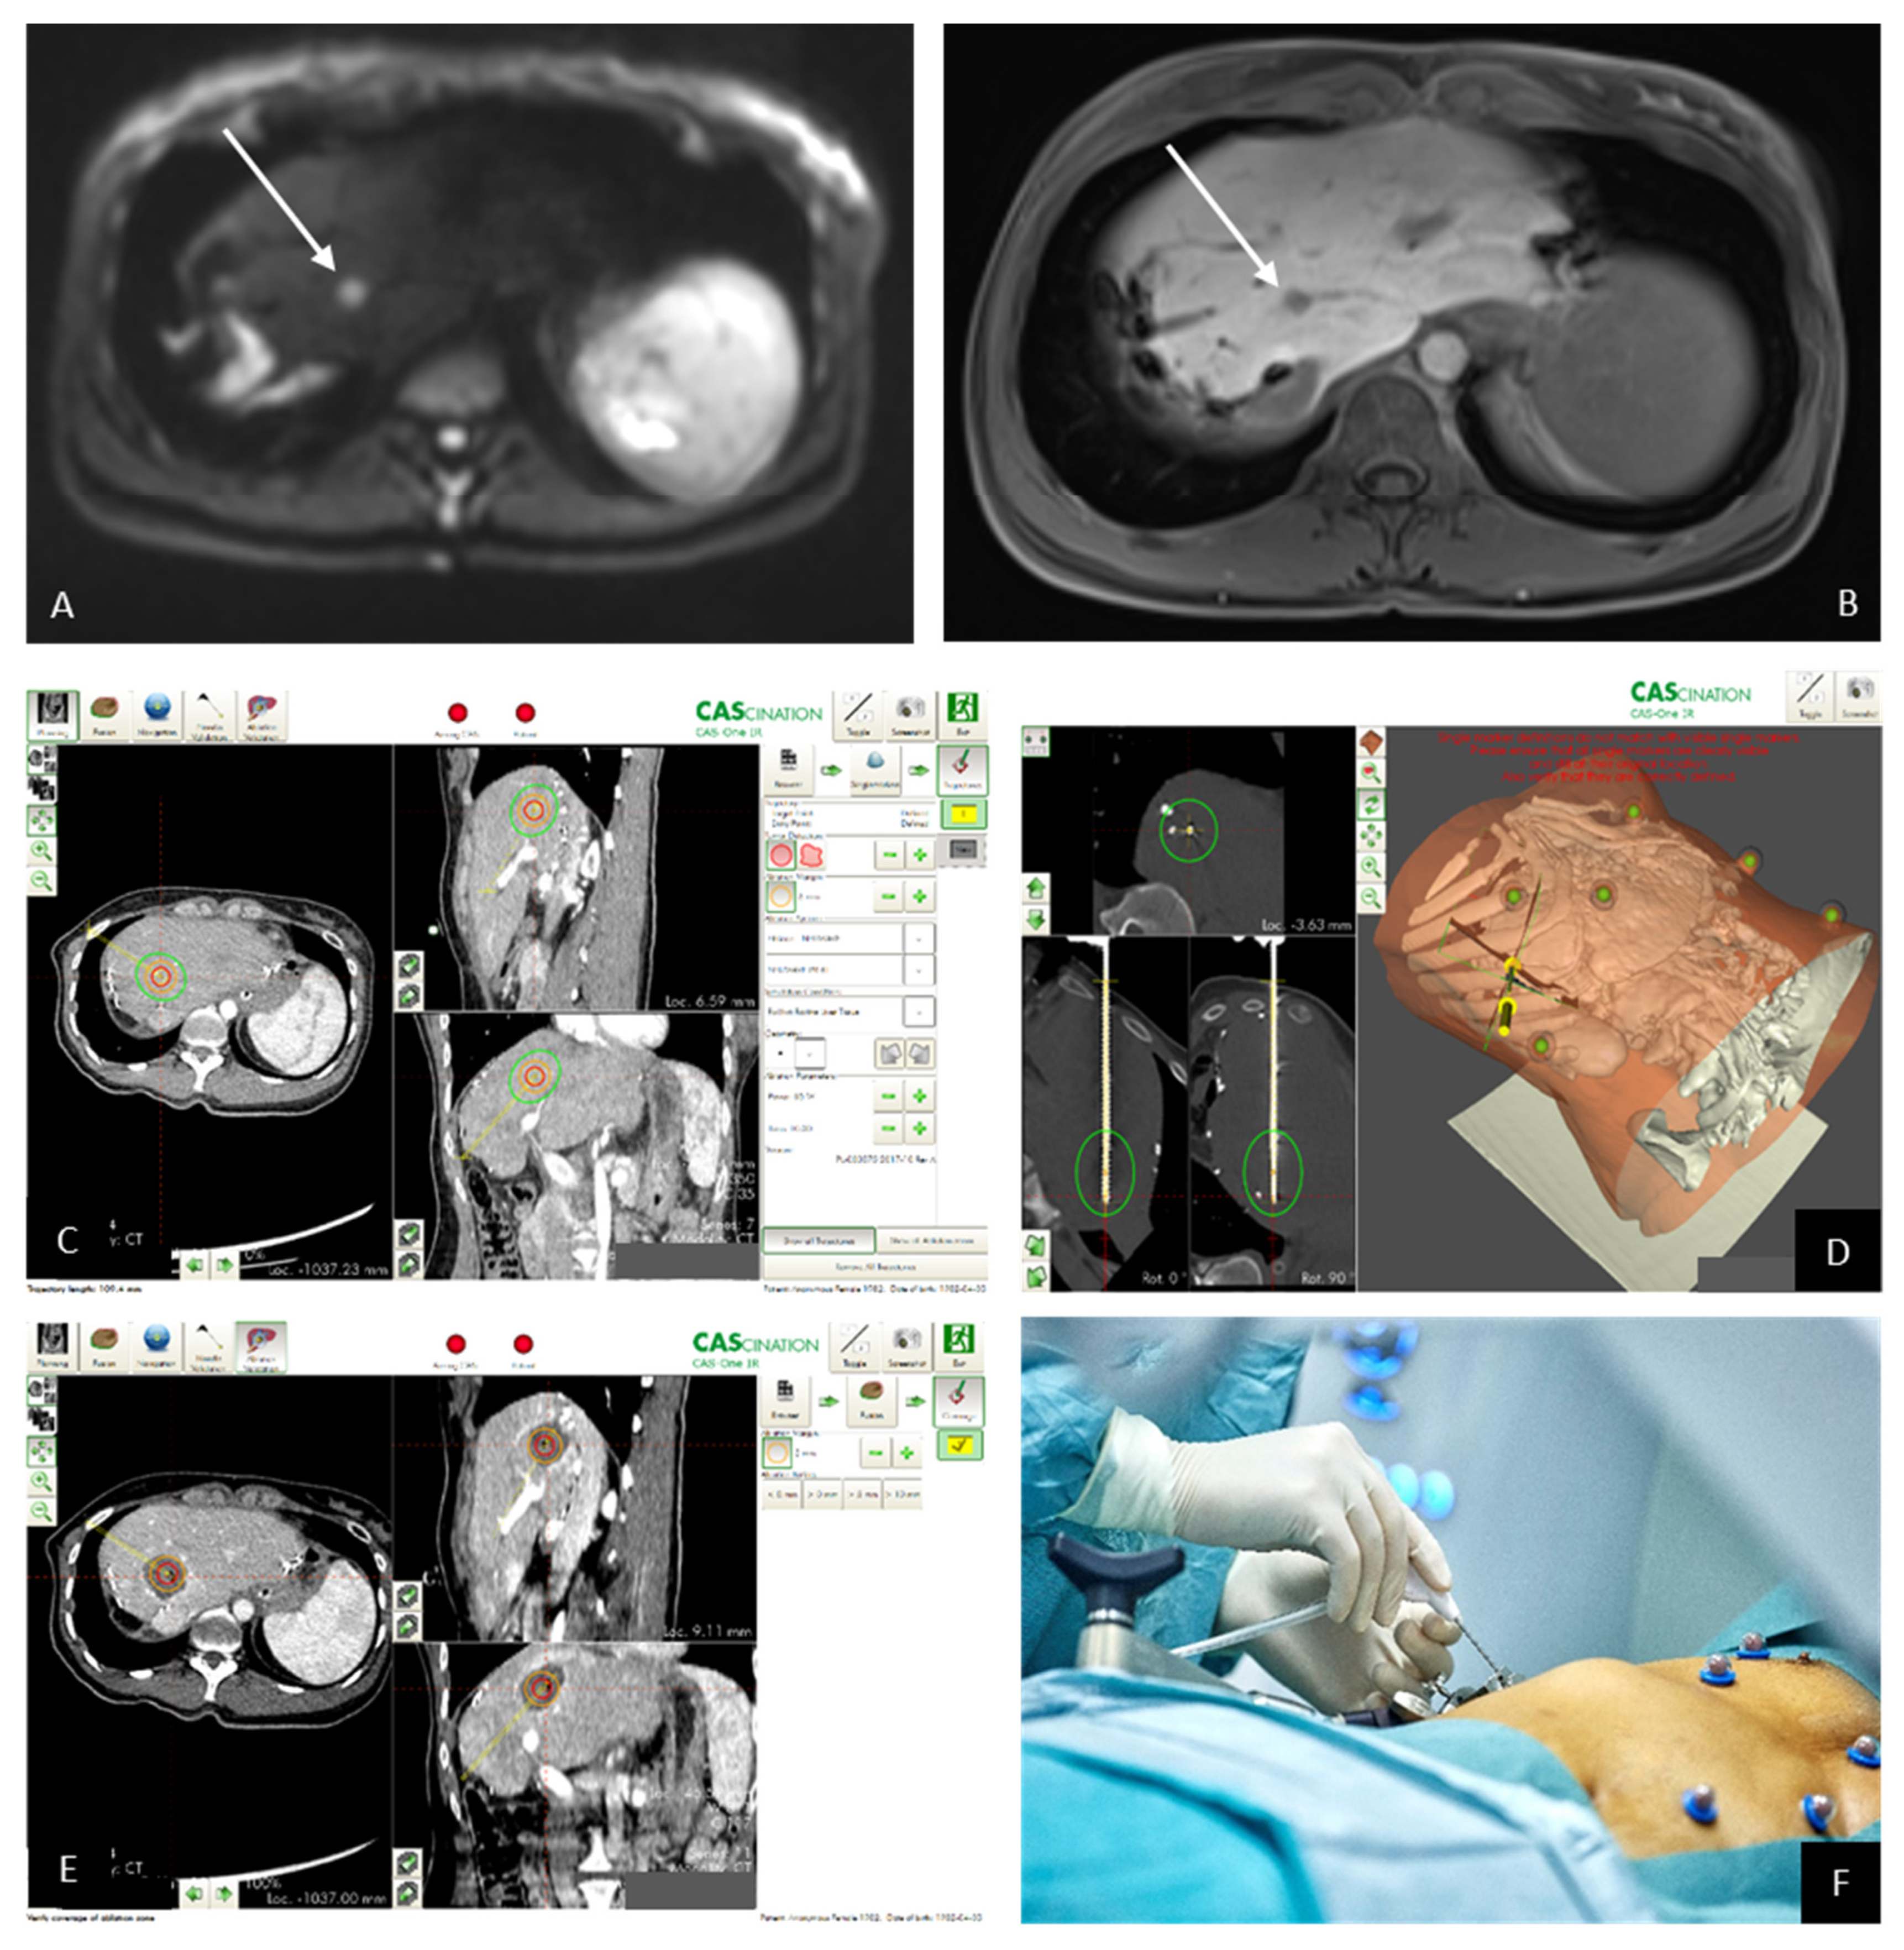

3.8. Own Patients with ICCA Treated by SMWA